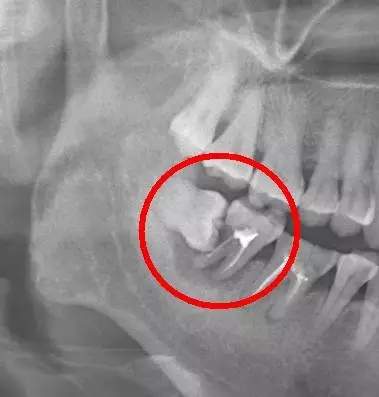

阻生智齒中典型的“秀恩愛,死得快”型,智齒因為萌出空間不足,造成傾斜阻生,斜靠在旁邊的牙齒上,把旁邊好好的鄰牙給直接頂壞掉。

640.webp (3).jpg

阻生智齒的幾種常見類型

口說無憑,上病例。來看下面這例

640.webp (4).jpg

這種情況就因為沒及時拔除智齒,最終的結(jié)果就是把鄰牙也拖下水,兩顆牙齒一起報銷,旁邊的第二恒磨牙本來就容易因為清潔不徹底齲壞的好么,還要無端被拖著陪葬,真是生存不易。更慘的是,鄰牙拔除之后,還必需要裝上一顆種植牙補上(我會告訴你裝一顆種植牙花費上萬是很正常的么),得不償失?。。?/span>

需要特別注意的是,鄰牙病變具有一定的隱蔽性,通常的情況是可能旁邊牙齒已經(jīng)被頂壞了,患者還沒有任何感覺,這就需要拍一張口腔 X 光片才能進行準確的診斷。